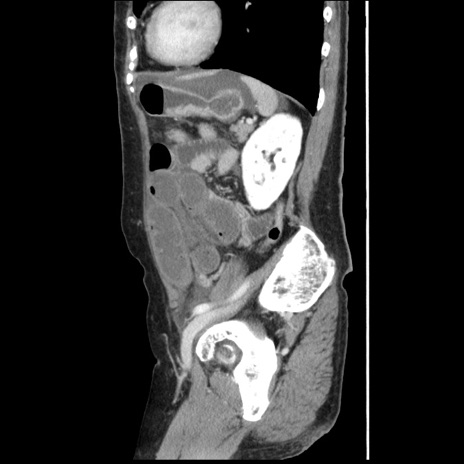

症例1(矢状断像)

【症例】80歳代女性

【主訴】腹痛

【現病歴】8時間前から腹痛あり来院。

【既往歴】糖尿病、脂質異常症、子宮体癌にて子宮全摘術

【身体所見】意識清明・会話良好だが腹痛で苦悶様、全腹部にわたって反跳痛と圧痛あり

【データ】WBC 13600、CRP 0.14、LDH 224、CK 90